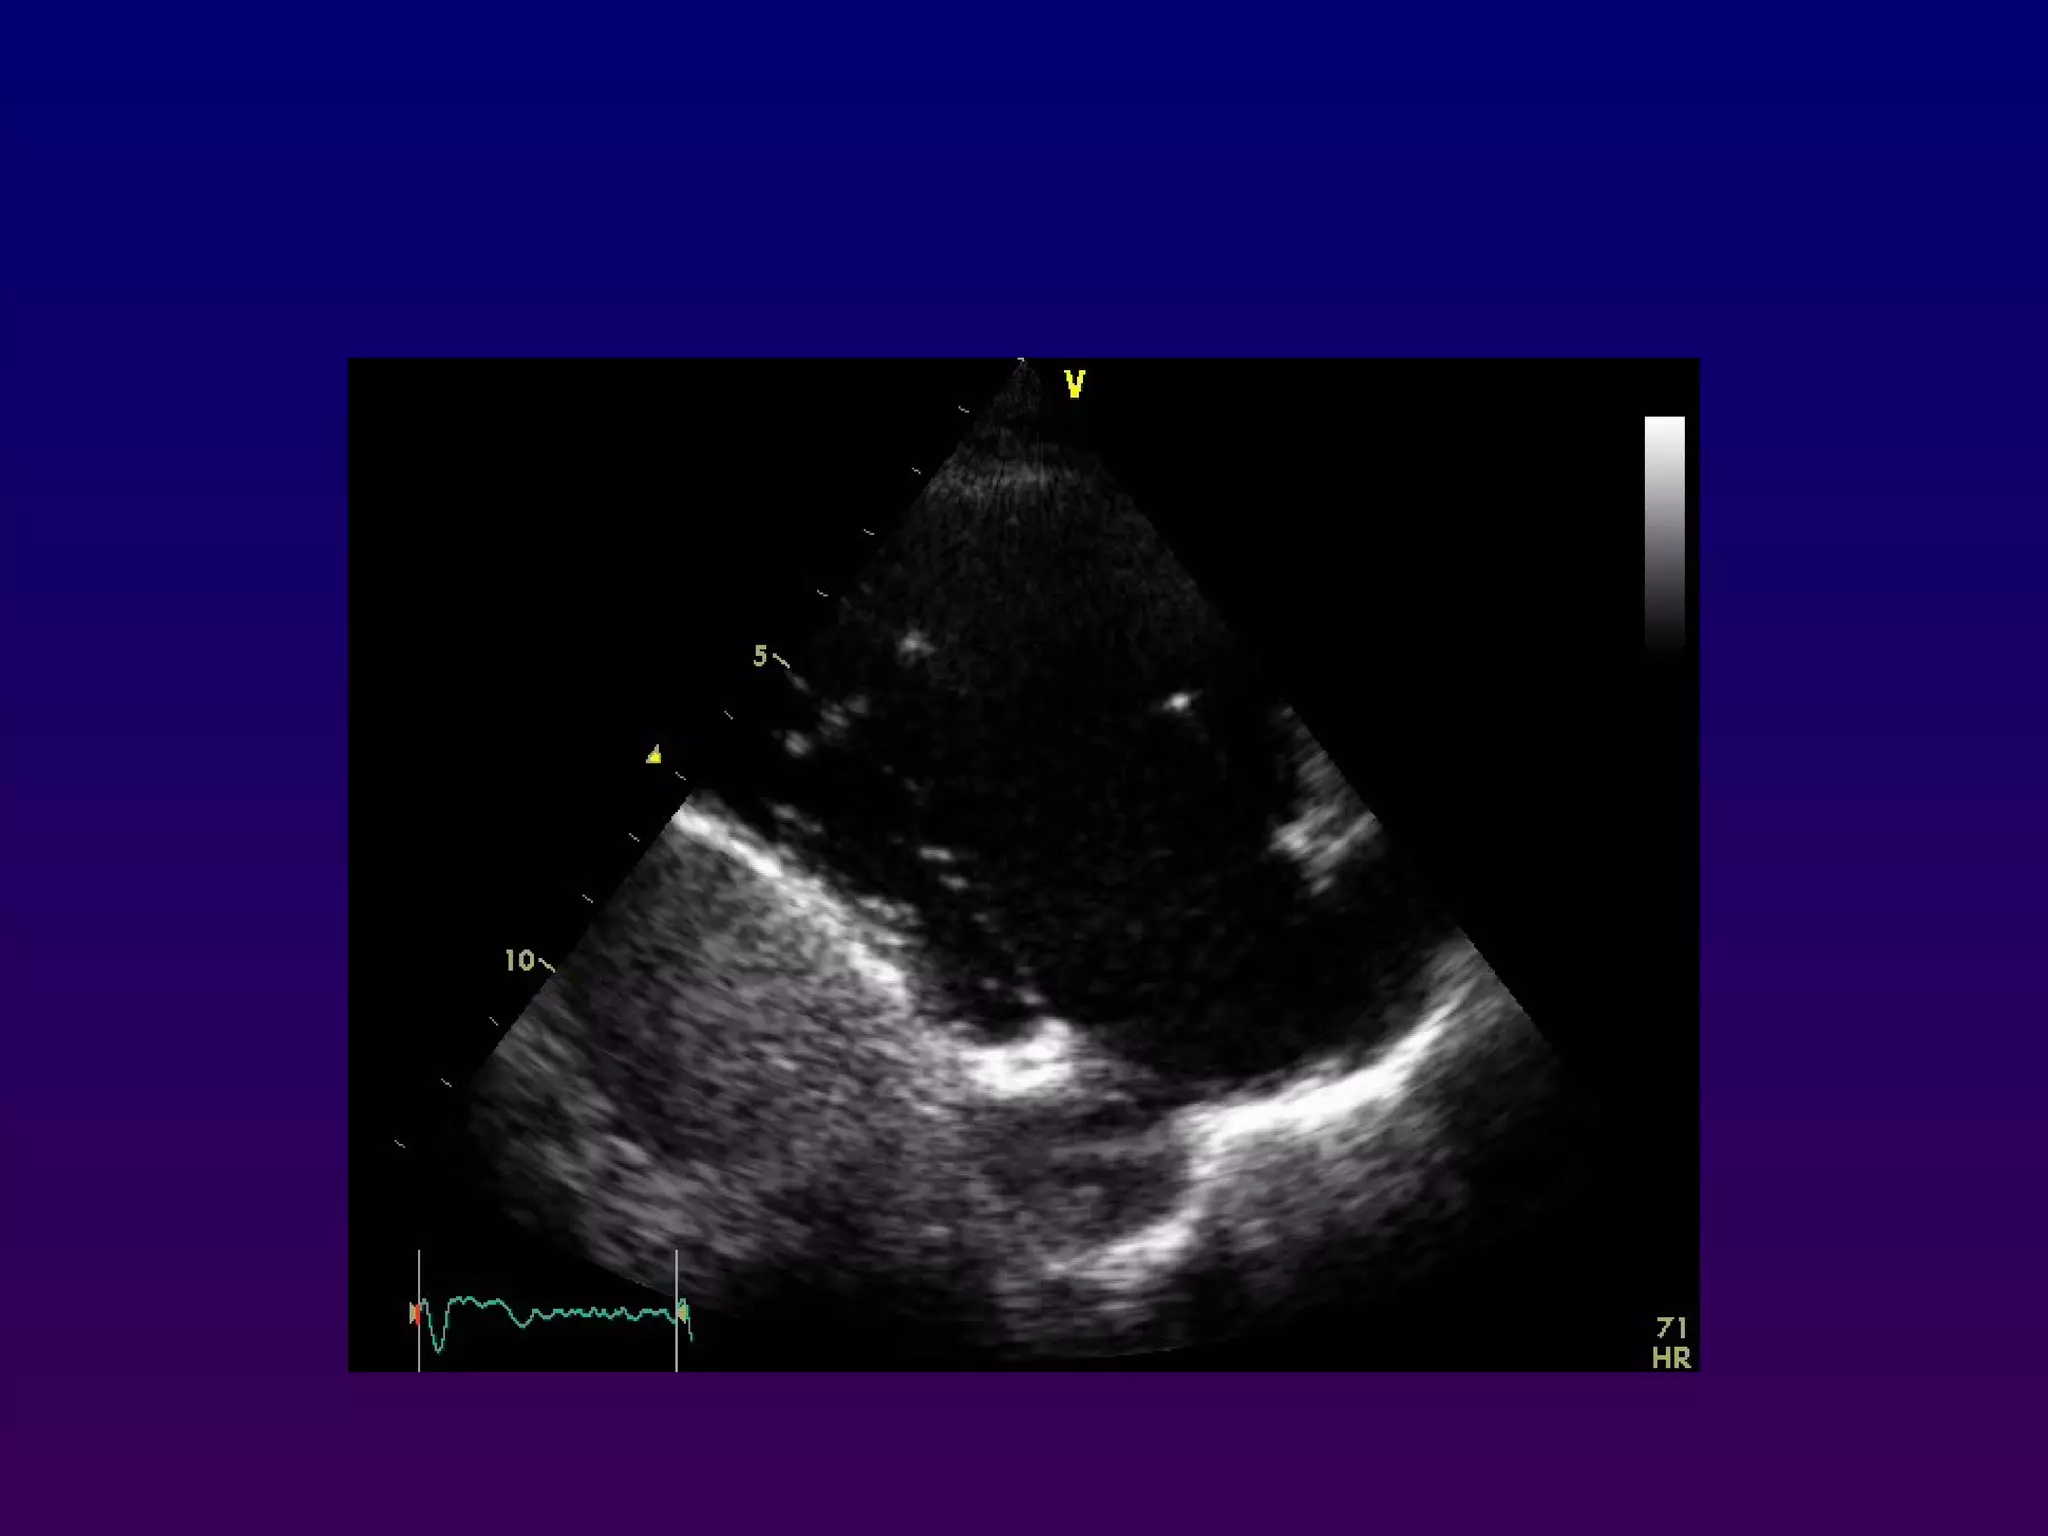

With the patient maintained in the left lateral

decubitus position, the transducer is placed near

In the apical four-chamber view, all four

chambers of the heart may be seen The left

ventricle appears as a truncated ellipse,RV

triangular with the interventricular septum, apex

formed by LV, and lateral walls visualized.

Apical four-chamber

With the patientmaintained in the left lateral decubitus position, the transducer is placed near the apex of the heart with an inferior orientation In the apical four-chamber view, all four chambers of the heart may be seen The left ventricle appears as a truncated ellipse,RV triangular with the interventricular septum, apex formed by LV, and lateral walls visualized. Apical four-chamber